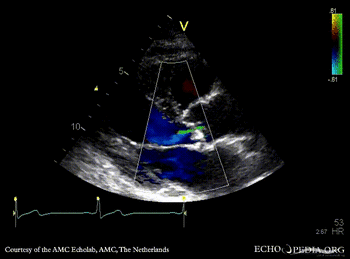

PSAX: severe aortic valve stenosis A5CH with Color: mild aortic regurgitation